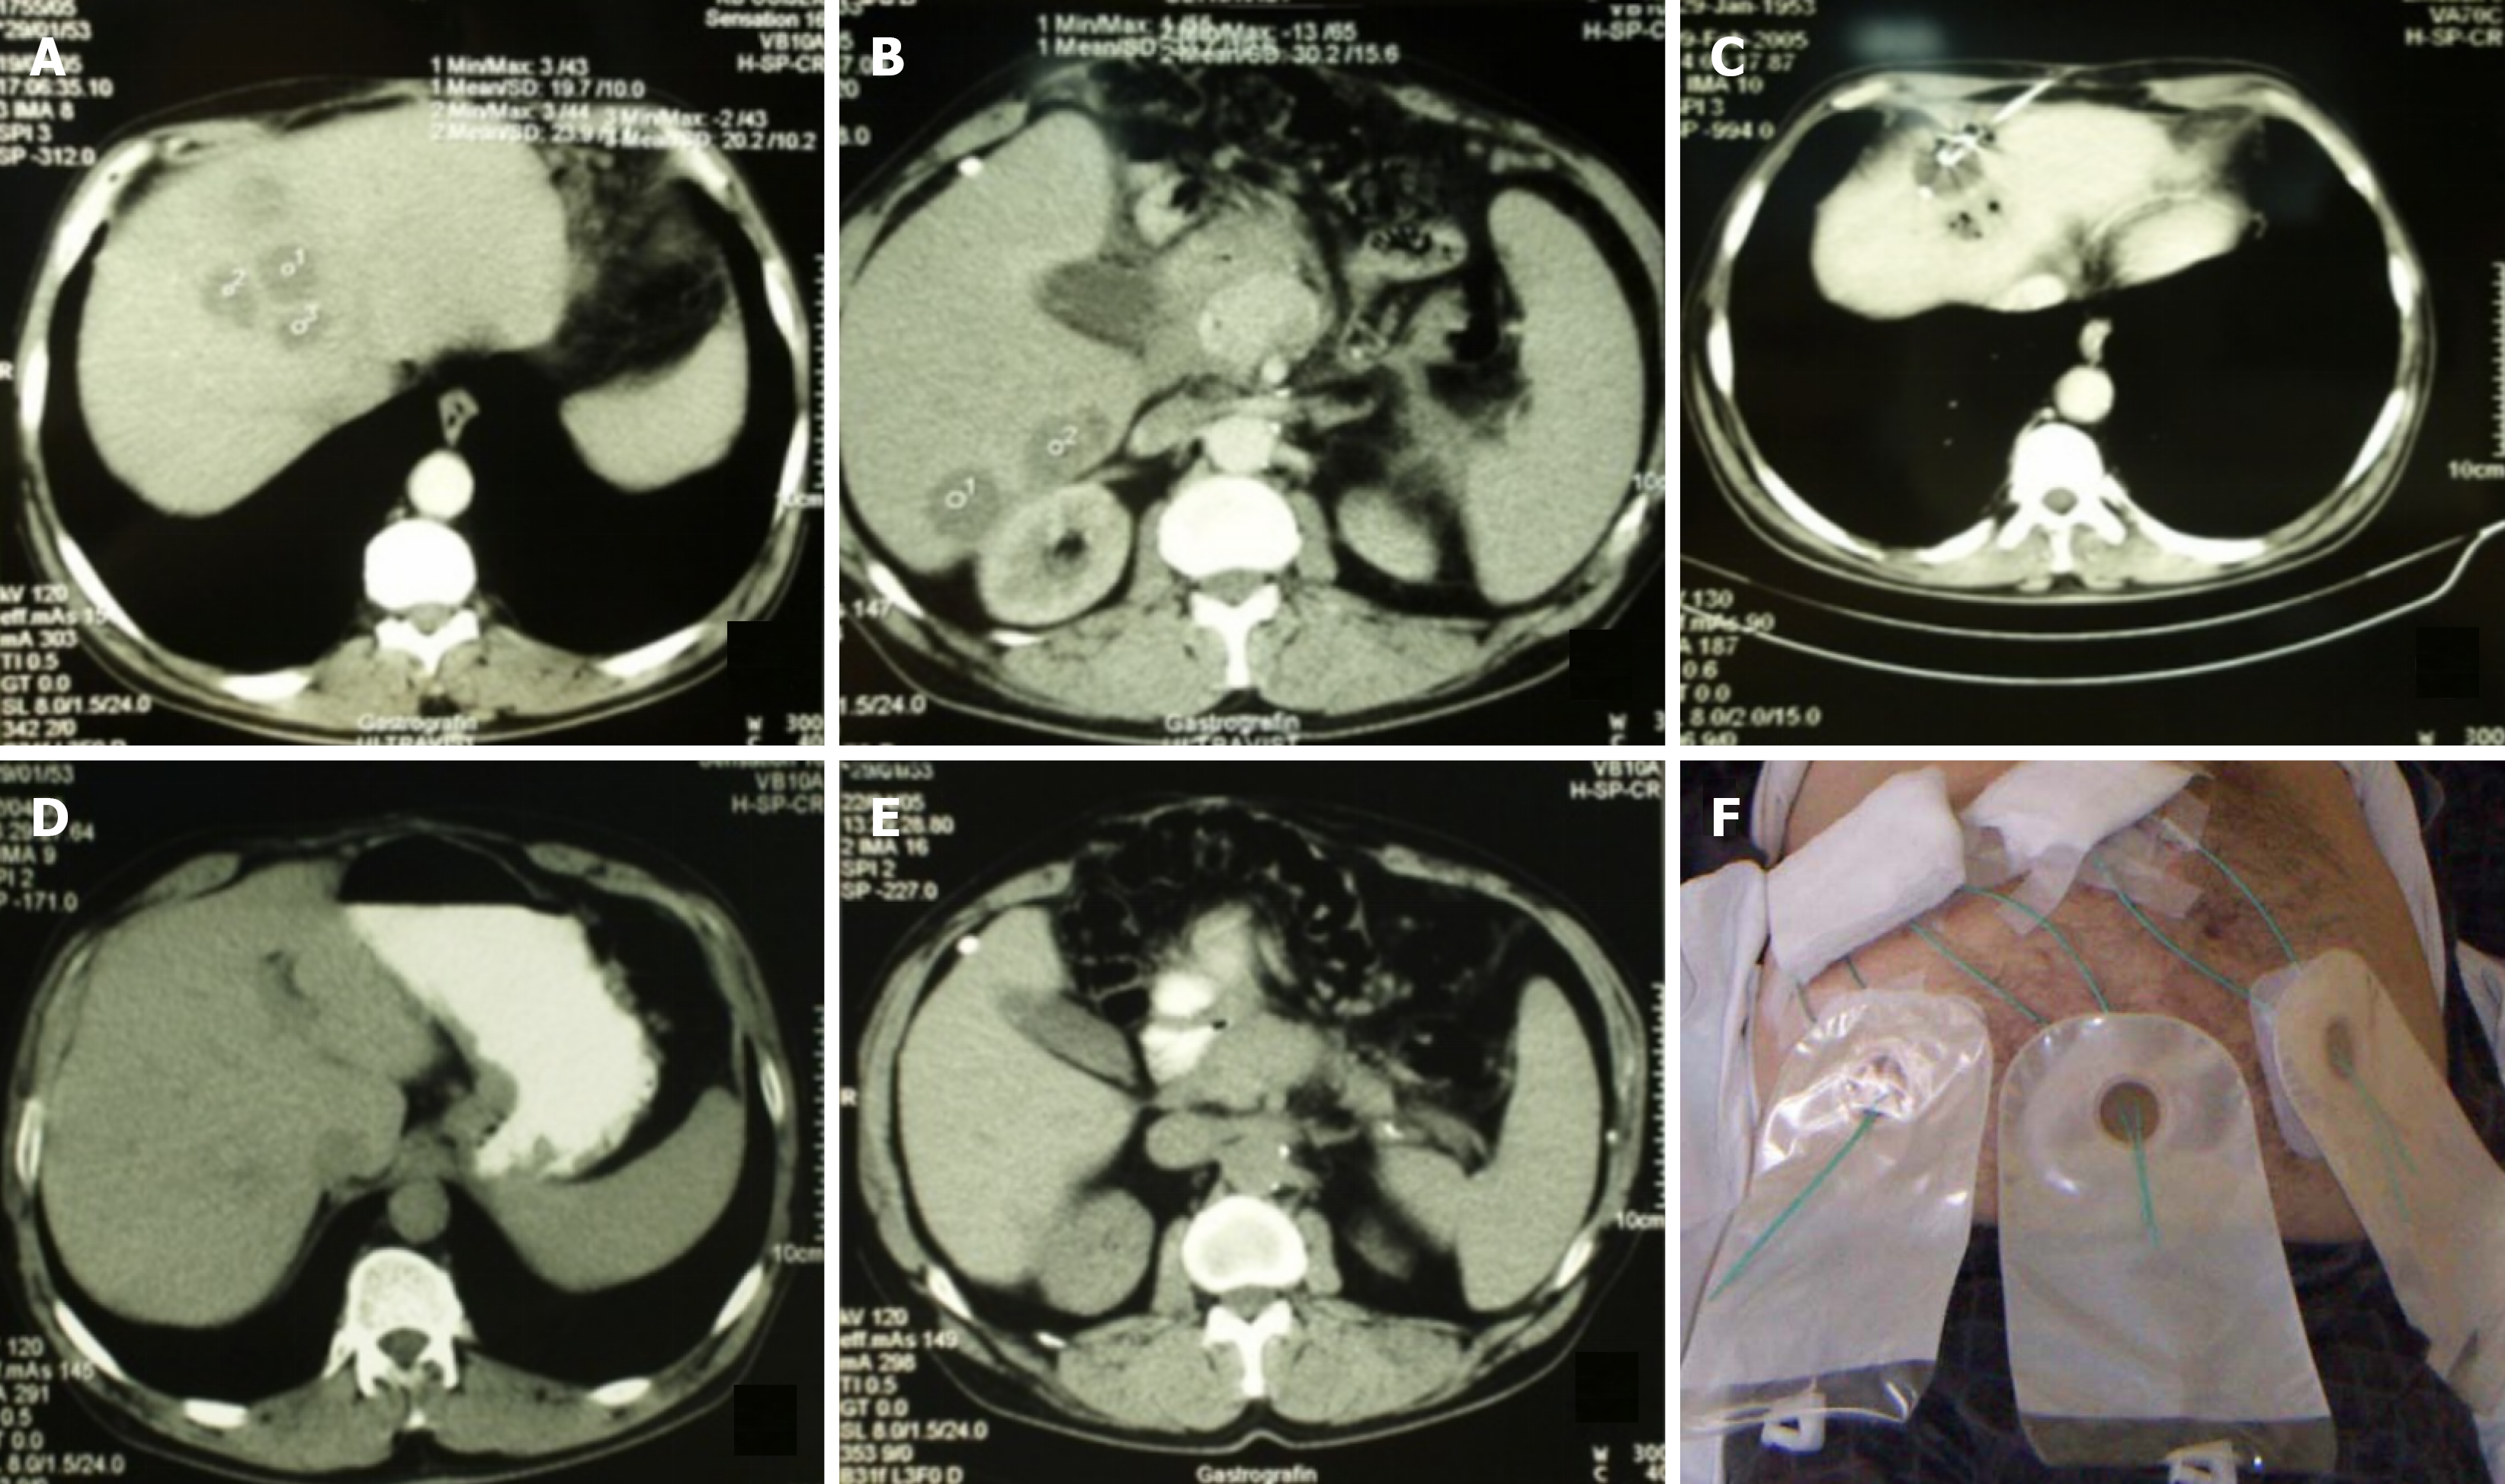

INDIVIDUALIZED APPROACHES: MATCHING TECHNIQUE TO PATIENT AND DISEASE

There is no standardized approach to the treatment of PLA, as the clinical and radiological heterogeneity among patients necessitates individualized therapeutic strategies tailored to both the characteristics of the abscess and the patient’s overall clinical condition. The choice between NA, CD, or surgical intervention should be based on a comprehensive assessment of abscess features - such as size, location, number, degree of encapsulation, and liquefaction - as well as the presence of patient comorbidities (Figures 1 and 2)[36,38,40].

Figure 2

Figure 2 Percutaneous drainage of a double abscess collection in the right liver lobe, formed two weeks after appendectomy. A: Two abscess collections in the right liver lobe; B: Transhepatic access to the abscess collection using the trocar technique; C: Vigorous irrigation of the abscess cavity with a 50/50 mixture of iodine and saline through a catheter; D: Scar formation in liver tissue three weeks post-intervention.

Among these factors, abscess size is one of the most widely recognized determinants in selecting the appropriate intervention. In general, abscesses measuring ≤ 5 cm are considered suitable for NA, whereas larger lesions (> 5 cm), or those showing incomplete resolution following NA, typically require CD[2,12]. However, anatomical location is also a crucial factor, as deeply situated abscesses in the posterior hepatic segments or near the hepatic hilum may pose technical challenges for percutaneous access and catheter placement (Figures 1 and 2)[2,29].

The stage of abscess maturation-ranging from solid to partially or fully liquefied-plays a critical role in determining the optimal percutaneous management strategy. Early-stage abscesses may appear poorly defined and heterogeneous on imaging; in such cases, aggressive catheter manipulation can increase the risk of parenchymal injury or bleeding, and less invasive US-guided NA is often preferred to minimize complications. Conversely, in well-formed, encapsulated, and liquefied abscesses, CD is considered both safe and more effective in achieving complete evacuation (Figures 1 and 2)[2,7,12,19].